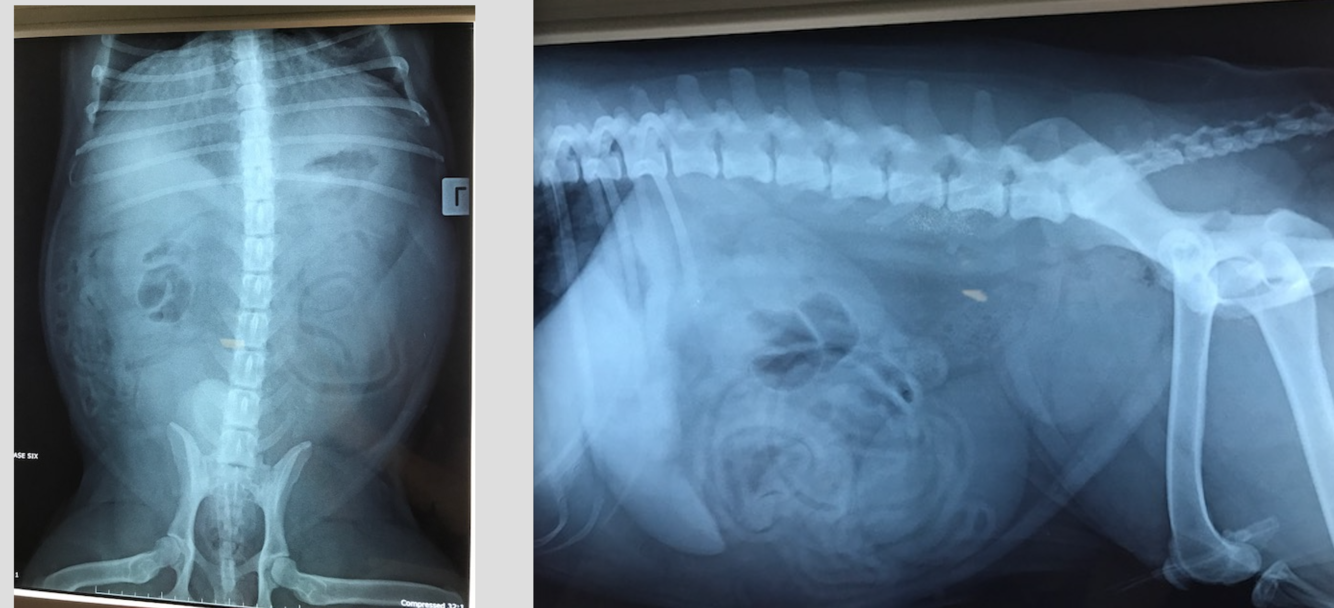

1 yo MN Burmese

5 week history of weight loss and reduced appetite

CE: Abdo palpation: pain on palpation with thickened intestinal loops/poss descending colon palpable. Estimate poss < 5% dehydrated.

DDX decreased intraserosal detail? Most likely?

Rule for assessing gastric distension?

Oval, comma shaped and C shapred SI throughout the mid abdomen? What is the rule for SI overdistension in the cat?

The distended loop of intestine containing fragmented gas opacities within the cranioventral abdomen on the lateral projection within the right cranial abdomen on the VD projection– do think this is SI or LI?

Stomach– no greater than 3 ICS– fundus typically 2 x wide as pylorus

11 yo FS Maltese Terrier

Not quite right for a couple days now, vomiting

HR RR WNL- pendulous abdomen, not painful on palpation. V+ and diarrhoea

DDX intraabdominal decreased serosal detail? Most likely?

Hepatomegaly- what are the rules for assessing liver ? DDX?

Gas distended SI…

Fragmented mineral opacity in the descending colon….